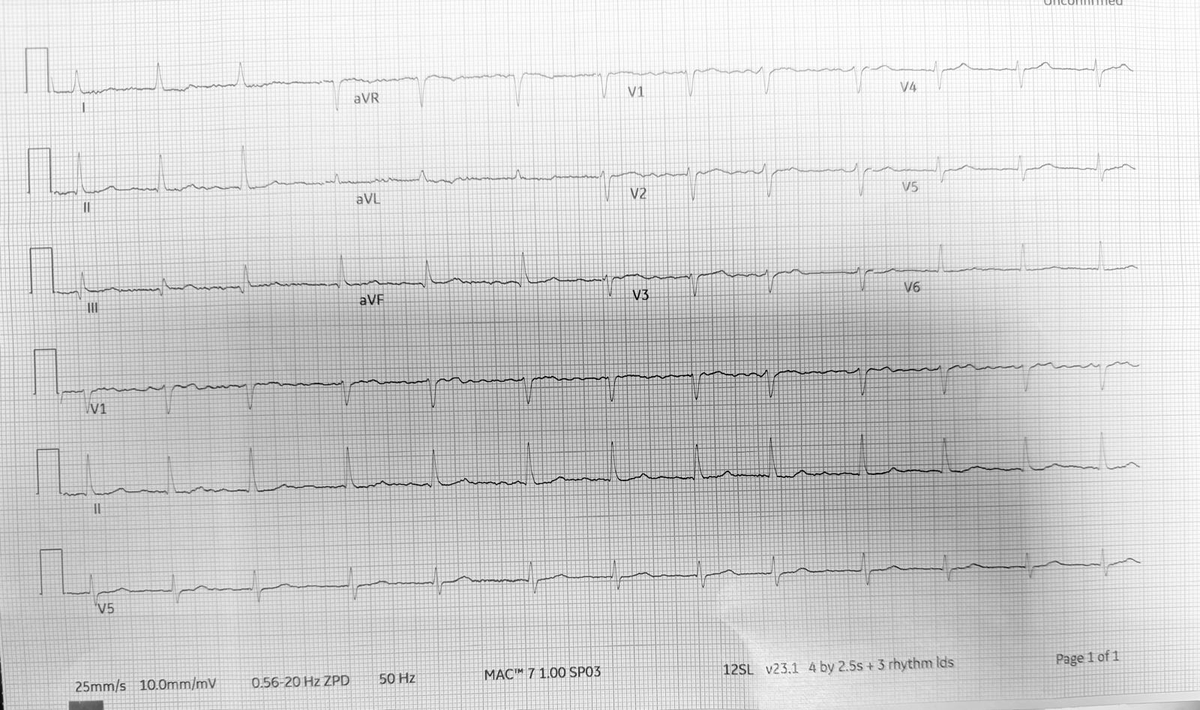

Most models interpret the ECG as normal sinus rhythm with some baseline artifact, but one model disagrees, calling it atrial fibrillation with rapid ventricular response and diffuse ischemic ST changes.